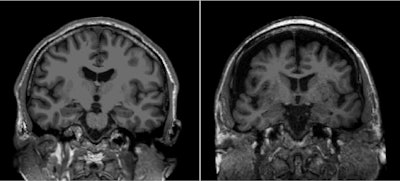

The authors reported that, at six-year follow-up, patients reporting social isolation via the Lubben scale had smaller hippocampus volumes and reduced cortical thickness on MR imaging. They also found that the higher the level of social isolation participants reported, the poorer their cognitive functions such as memory, processing speed, and executive capability.